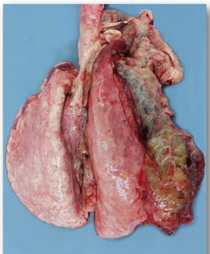

Pleurisy

A form of fibrinous pneumonia.

General rule

Drier beige deposits = more longstanding lesions